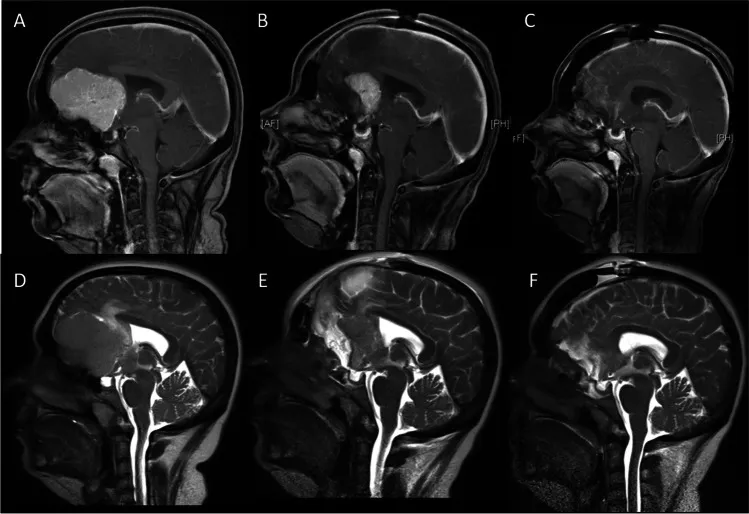

图1:矢状位磁共振成像。增强T1加权(A-C)与T2加权(D-F)图像显示瘤周水肿情况。A、D:术前图像。B、E:首次术后第一天,显示残留的壳状肿瘤。C、F:第二次术后第一天,显示肿瘤已完全切除。

第一阶段:首先实施双额开颅,继而选择右侧半球间入路。在显微外科技术辅助下切开大脑镰,切除大约80%的肿瘤主体部分,刻意保留一个壳状的肿瘤残腔。此阶段会将视神经显露出来,作为二期手术的重要解剖标志。但肿瘤的侧方边界以及累及大脑前动脉复合体背侧的部分,在此阶段不予分离。

第二阶段:待患者从一期手术中恢复,且脑水肿明显消退之后,进行二期手术。此阶段目标为将残余的肿瘤组织完全切除,并同期完成硬脑膜修补与颅骨成形术。